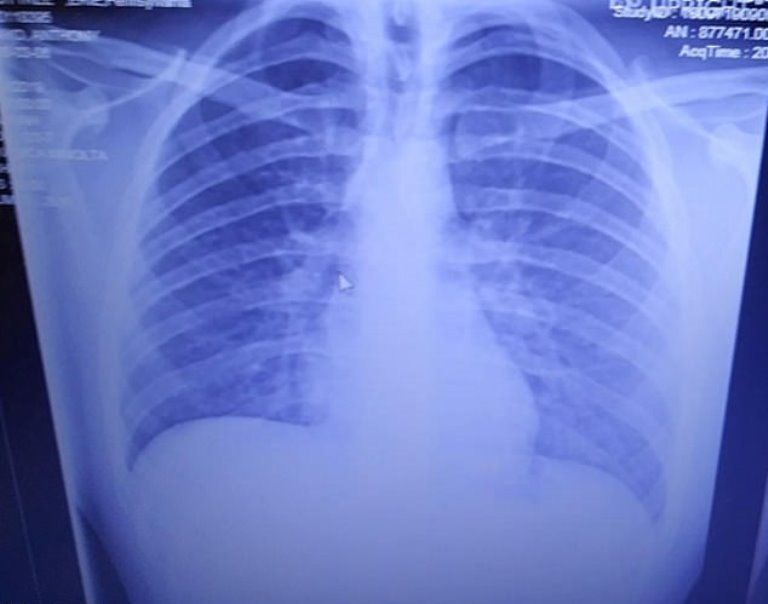

Scans revealed how vaping left his lungs filled with solidified oil that rendered him unable to breathe independently.

Doctors were shocked to discover his lungs were severely blocked with solidified vape oil, which they compared to hardened grease from frying bacon.

The condition had caused the teen, who has vaped for two years, to have ‘the lungs of a 60-year-old, 2-pack-a-day, smoker.’

Anthony’s mother, Tanya, also wrote: “A warning for those in denial. This is what vaping looks like when your otherwise healthy 19-year-old is admitted into the ICU.

“Left lung [is] about 80 per cent congested and right is about 50 per cent, oxygen level was 37.

“According to the doctor this is showing areas that have essentially solidified like bacon grease.

“The pulmonary doctor said he had seen dead people with a higher oxygen level. A full recovery is uncertain… Only time will tell.”